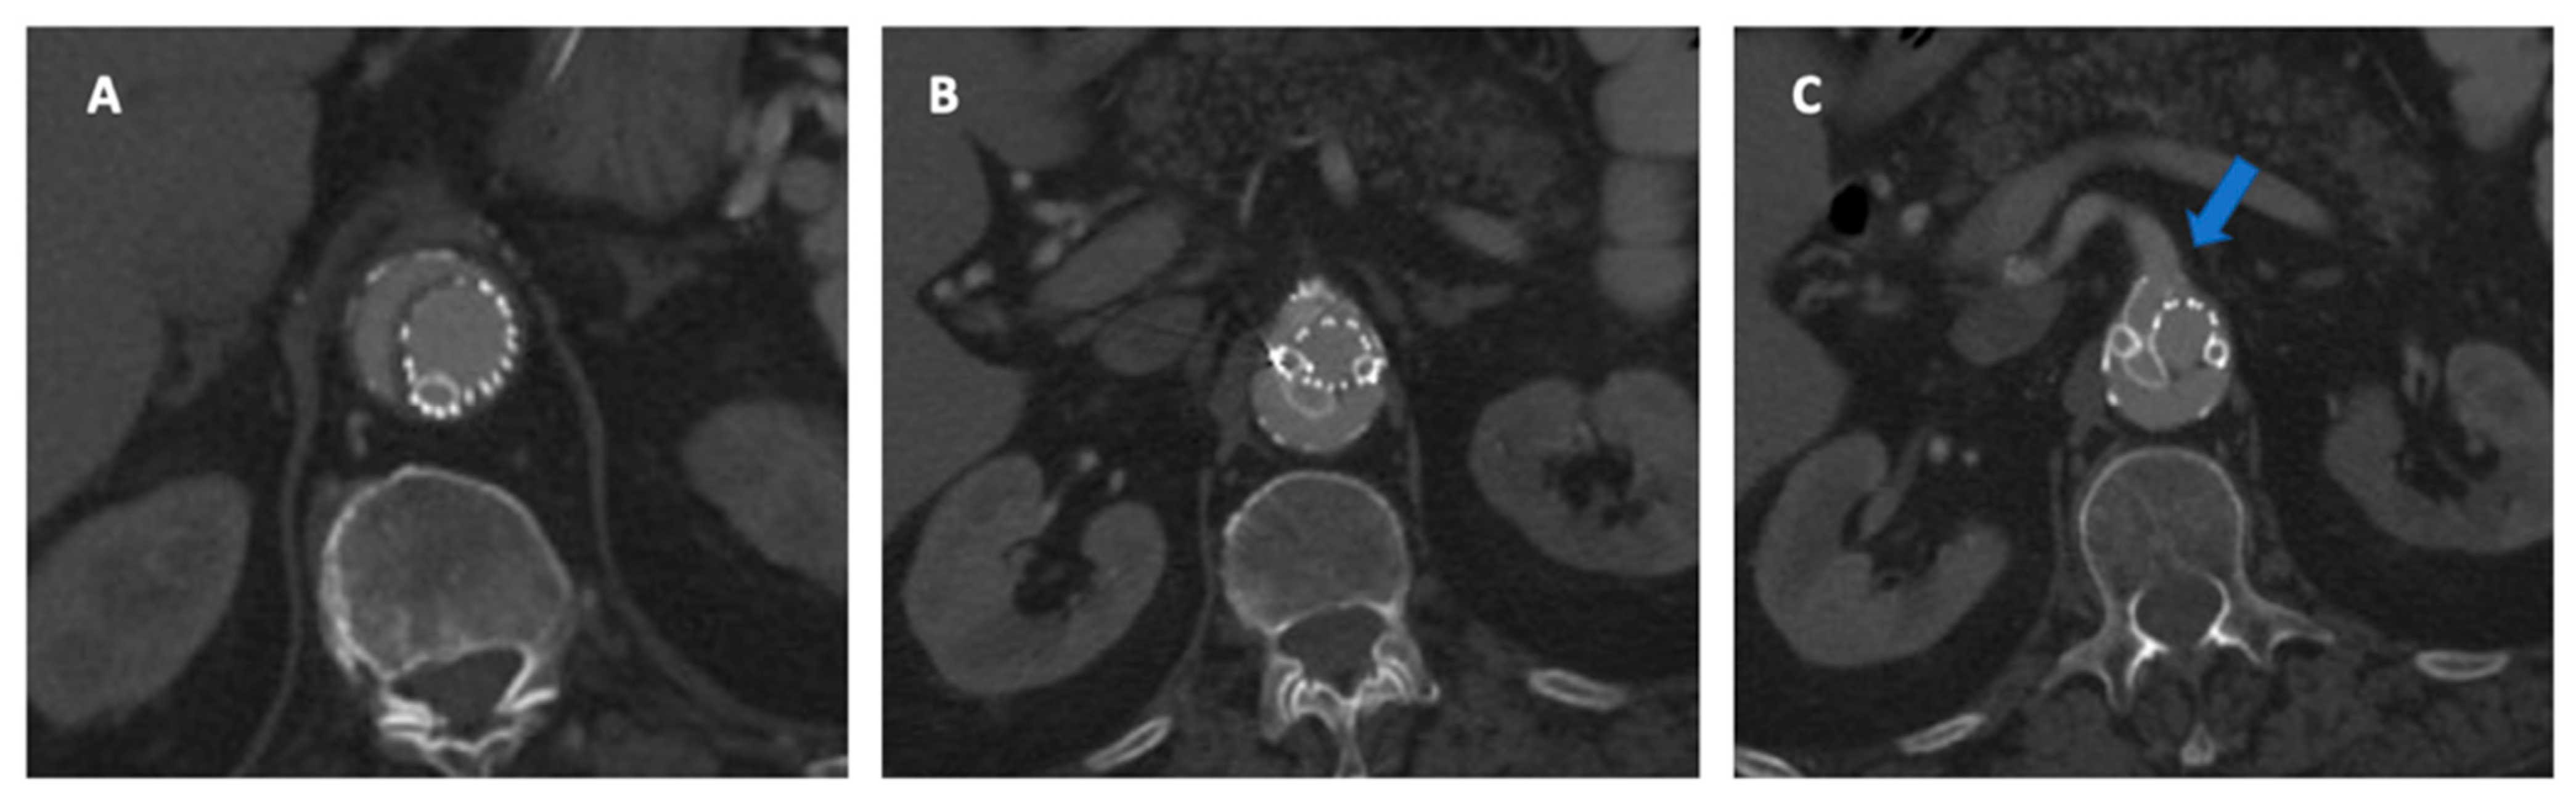

The use of diameter reducing ties allows for graft manipulation with partial deployment to mitigate this risk. A branched endograft allows a wider margin of tolerance for main body positioning compared to FEVAR, although the incorrect deployment of the endograft may still happen (Figure 7).

Figure 7.

During this procedure, the branched endograft was positioned incorrectly (turned 180°). Note in (A,B) the posterior origin of the branches for celiac trunk and superior mesenteric artery, respectively. In (C), there is evidence of a type 1C endoleak due to an inadequate sealing zone in the superior mesenteric artery (blue arrow).